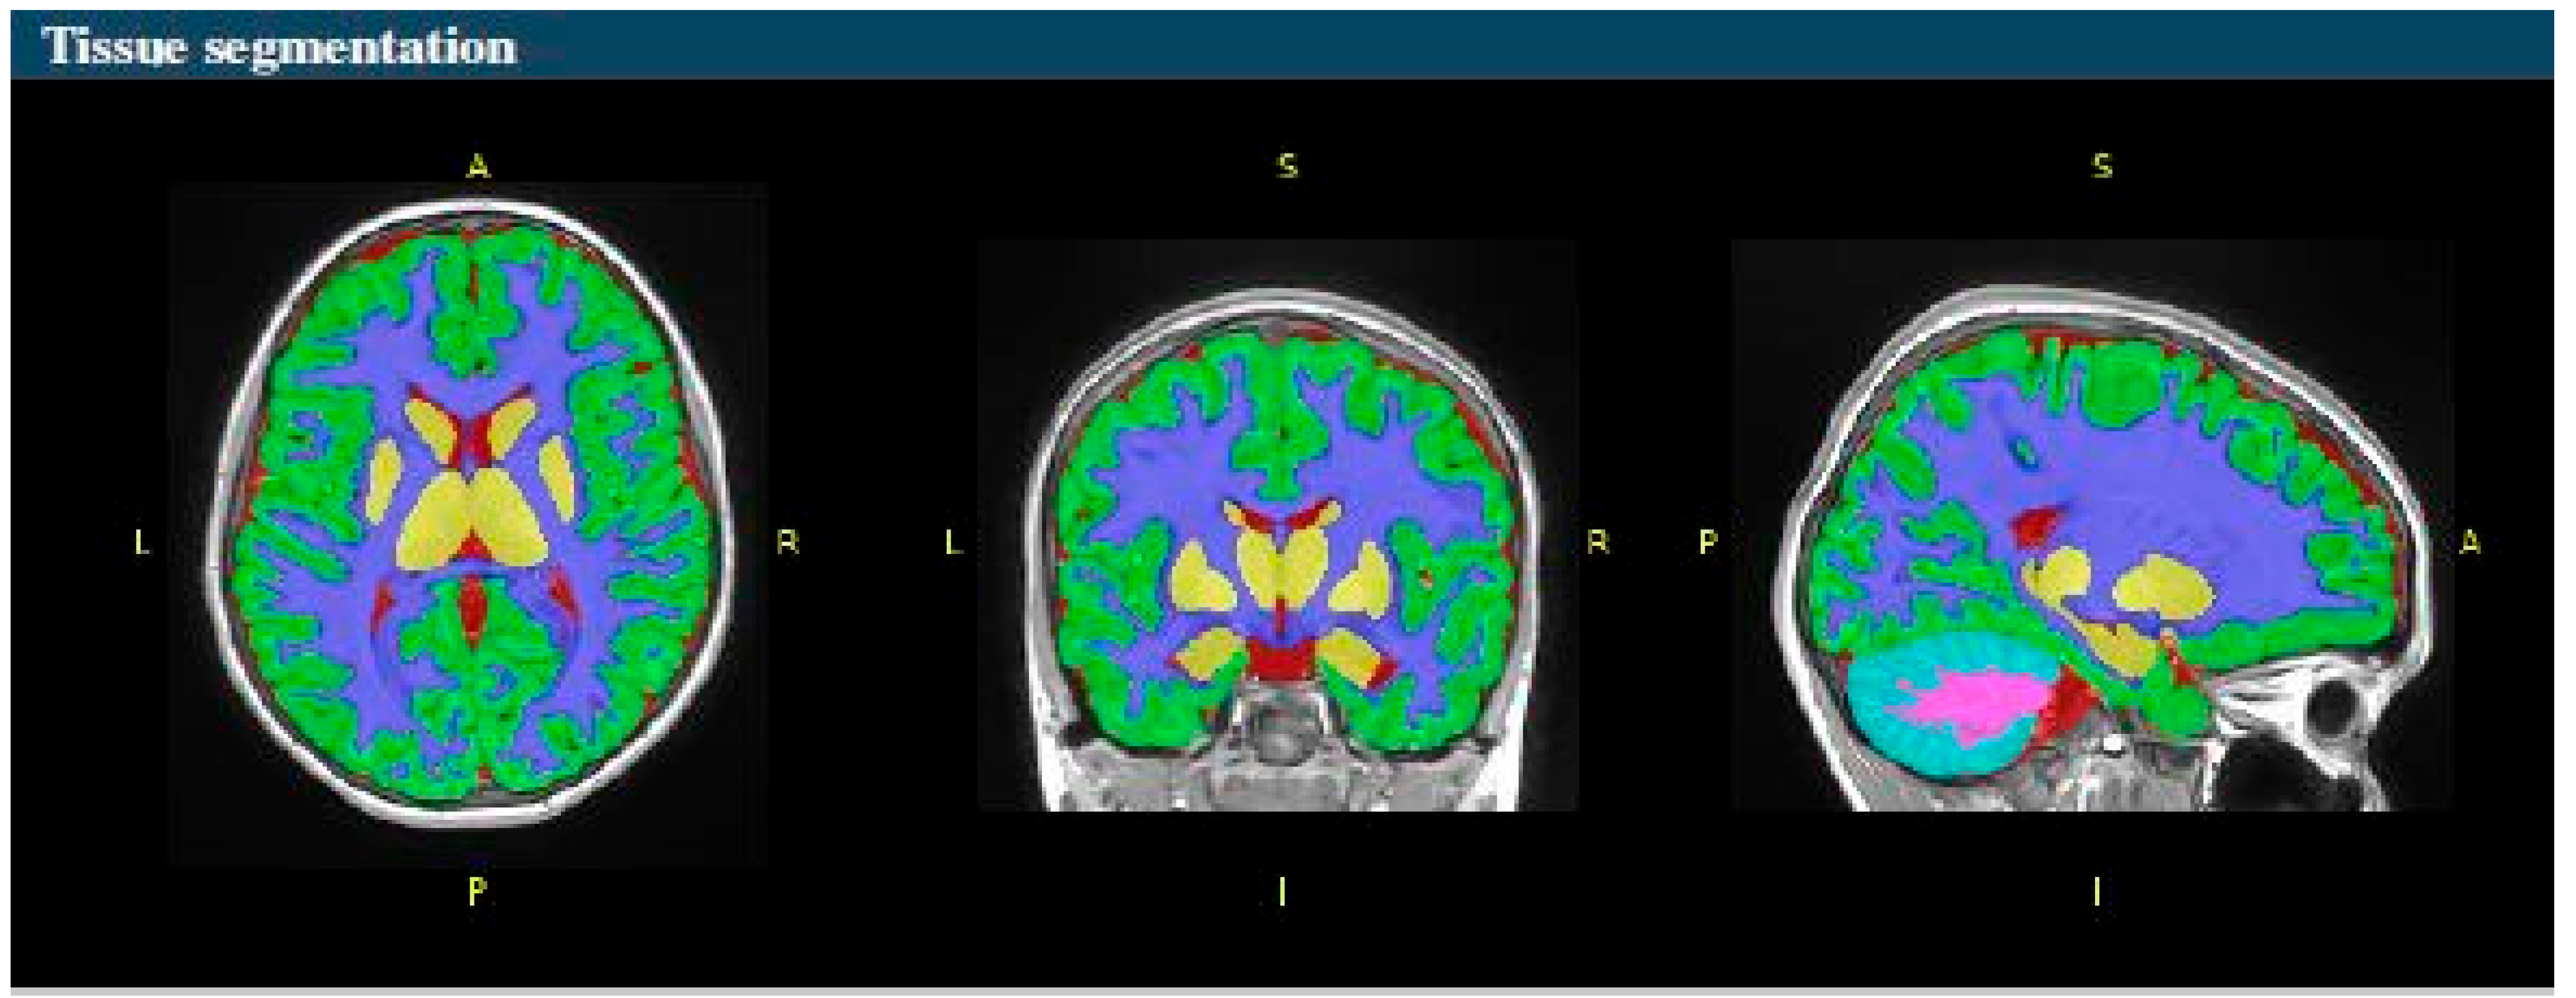

- Tissue classification and structure segmentation: volBrain employs a sophisticated segmentation process based on multi-atlas patch-based label fusion to classify various brain tissues (e.g., white matter, gray matter, cerebrospinal fluid) and segment key brain structures. This non-local label fusion method ensures that the segmentation is both accurate and computationally efficient.